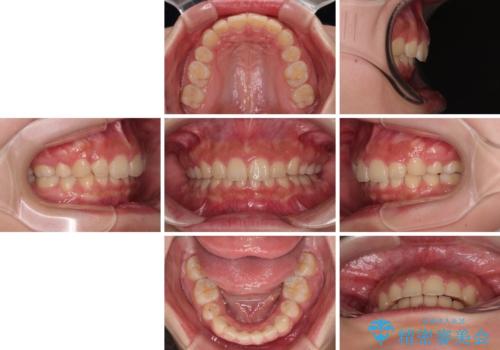

事前の予想通り、長期間を要する治療となりましたが、横顔の印象が劇的に変化し、患者様には大変満足していただきました。